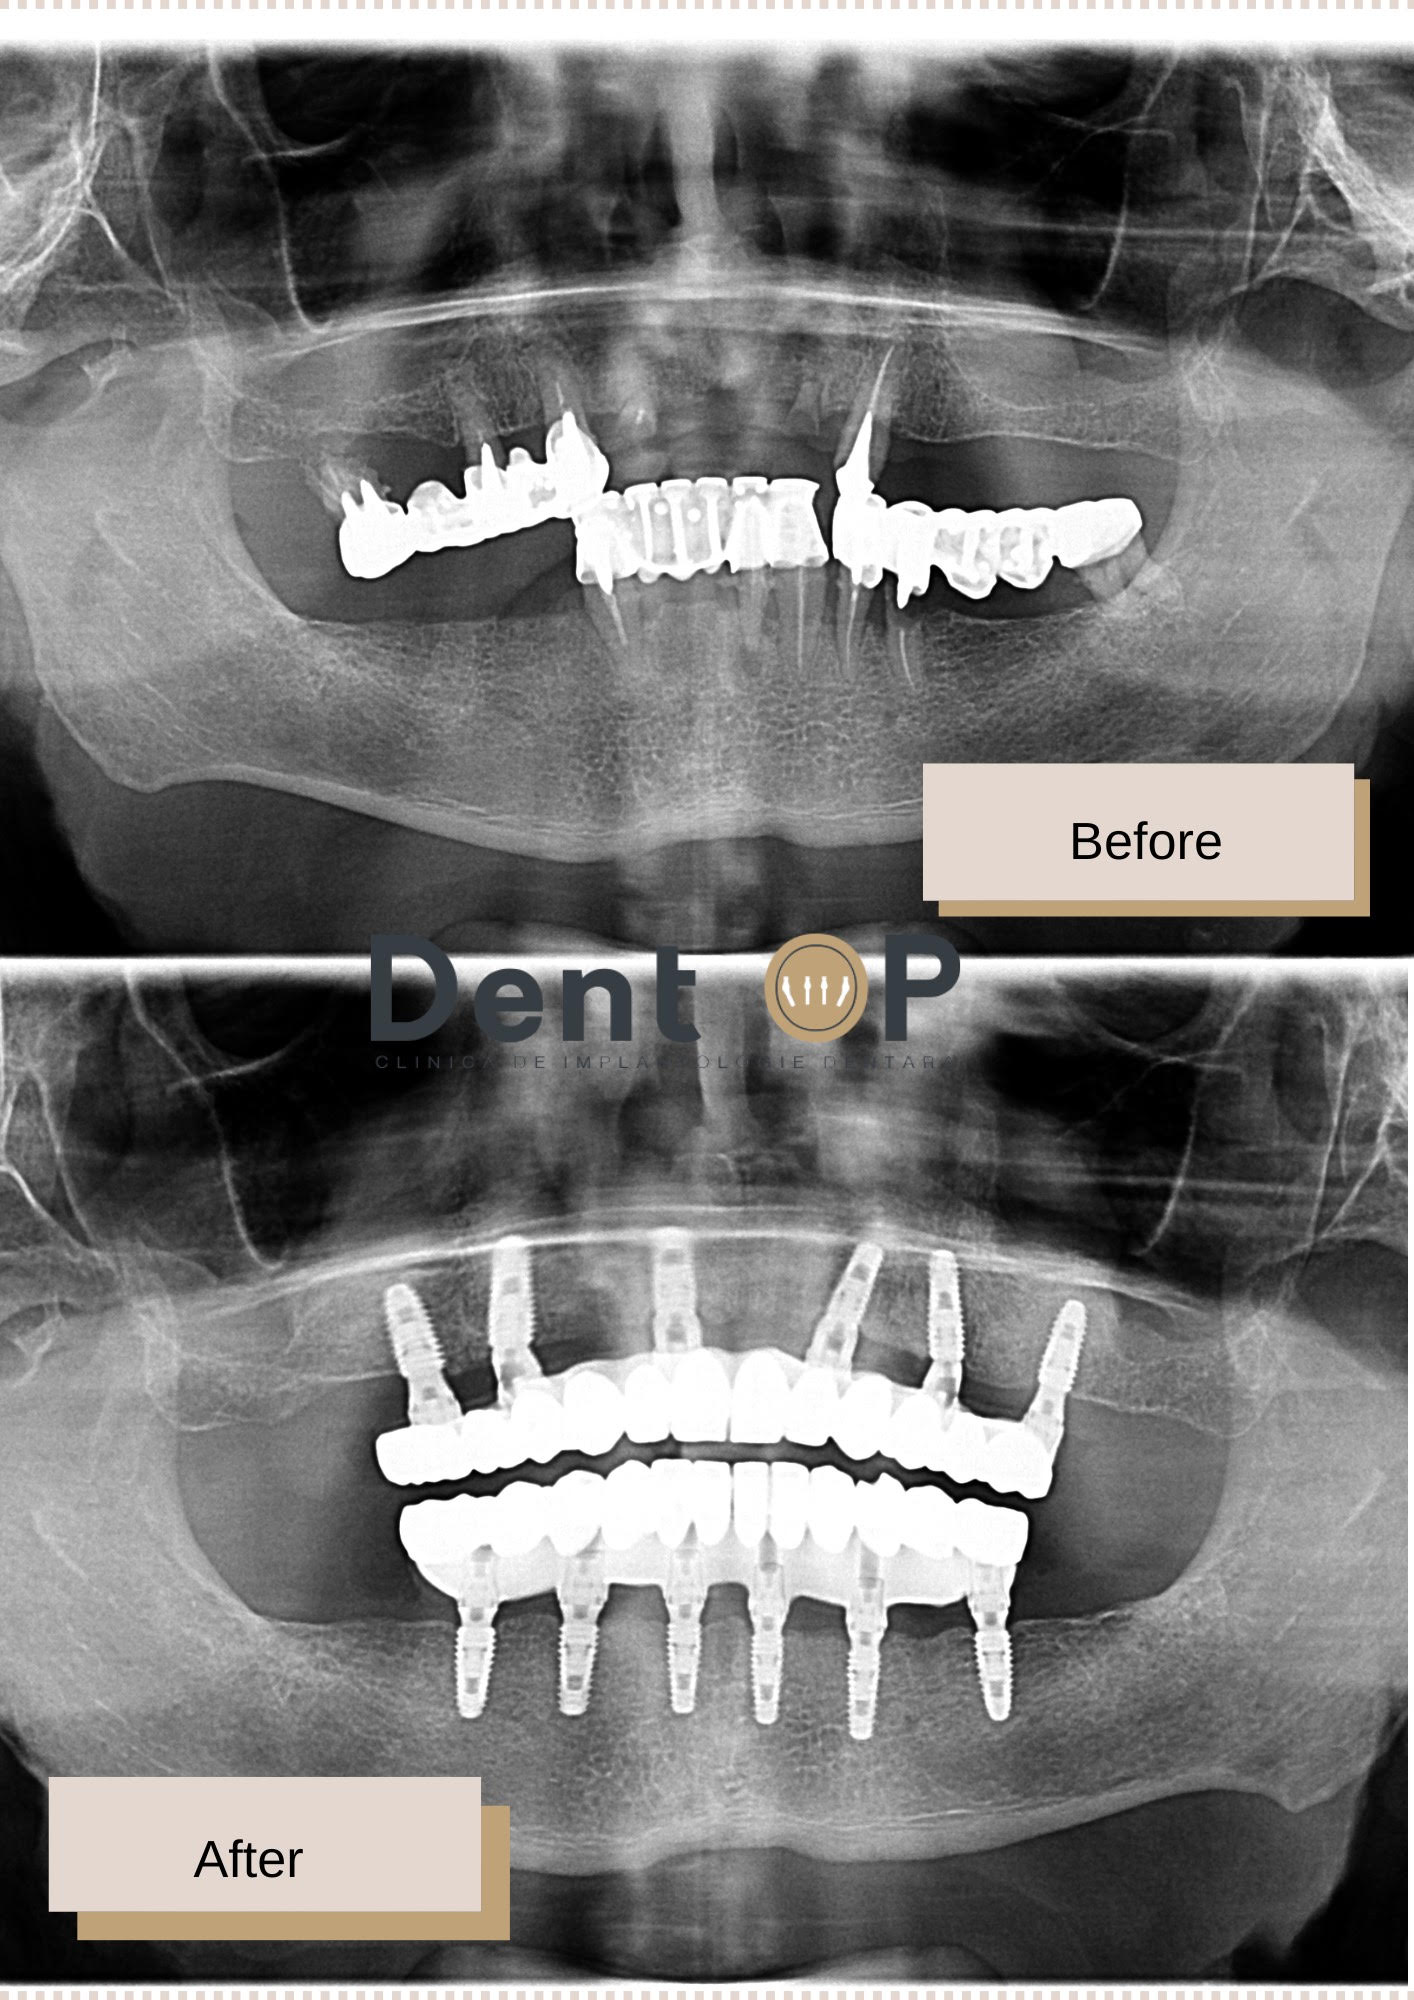

În cadrul primei consultații, Dr Cazacu Corrado, Medic Specialist Chirurgie Dento-Alveolară i-a propus tratamentul cu 12 implanturi dentare. Pacientul a înțeles planul de tratament și a acordat încredere echipei noastre. Astfel, în cadrul unei singure ședințe cu Sedare Conștientă a primit 12 implanturi dentare, iar în a doua zi o lucrare provizorie.

La 6 luni s-a fixat și lucrarea finală, după o serie de probe în care pacientul a fost ajutat să-și aleagă aspectul dinților finali. Rezultatul său este uimitor, iar pacientul este mulțumit și fericit că-și poate relua viața socială și masticația.